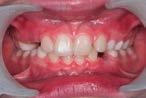

Evan Case treated with EF Class II 2 Steps

Treatment time: 12 months

Wearing of EF Class II 2 Steps for 3 months

Results: improved overhang without rabbiting

…

then

Wearing of EF Class II Standard for 3 months

Results: improvement in overhang, then overlay

with EF Class II Standard …

with EF T Slim

Wearing of EF T Slim for 6 months

Results: Class II corrected • Waiting for lateral sectors (1 year after the start of treatment)